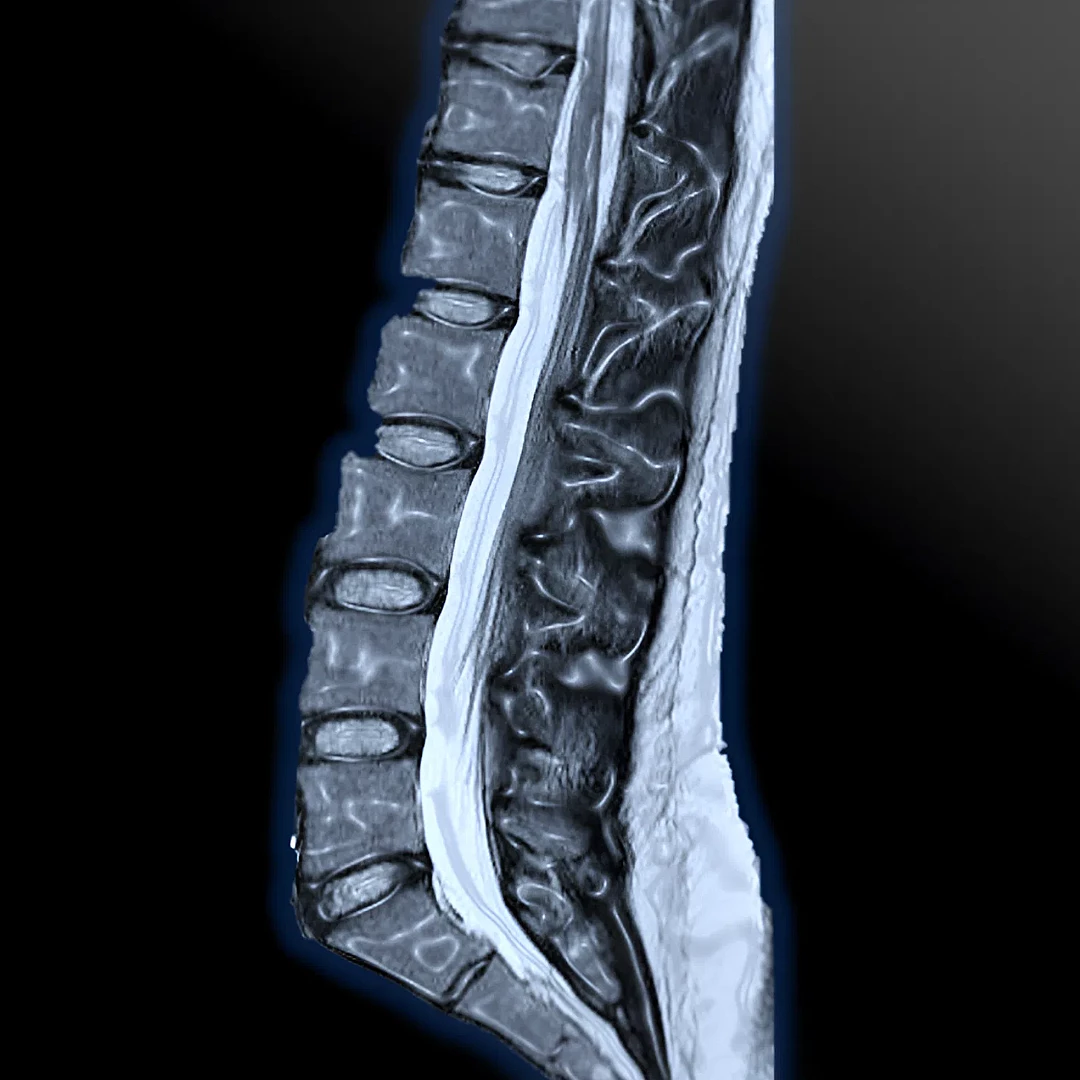

Advanced Spinal MRI offers high-resolution imaging of the spine to detect disc issues, nerve compression, tumors, or inflammation. It ensures precise diagnosis for back and neck pain, sciatica, and other spinal conditions.